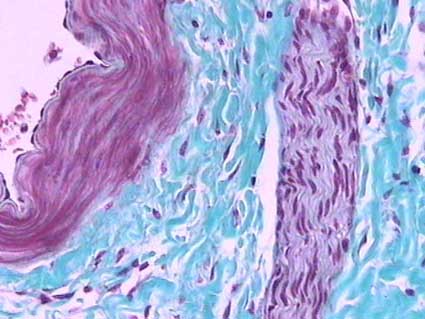

Figura 4. Las tinciones en las que se resalta el colágeno permiten identificar mejor el tejido intersticial. Aquí se ve de color verde, rodeando una arteria (izquierda) y un nervio (derecha). (Tricrómico de Gomori, X300).